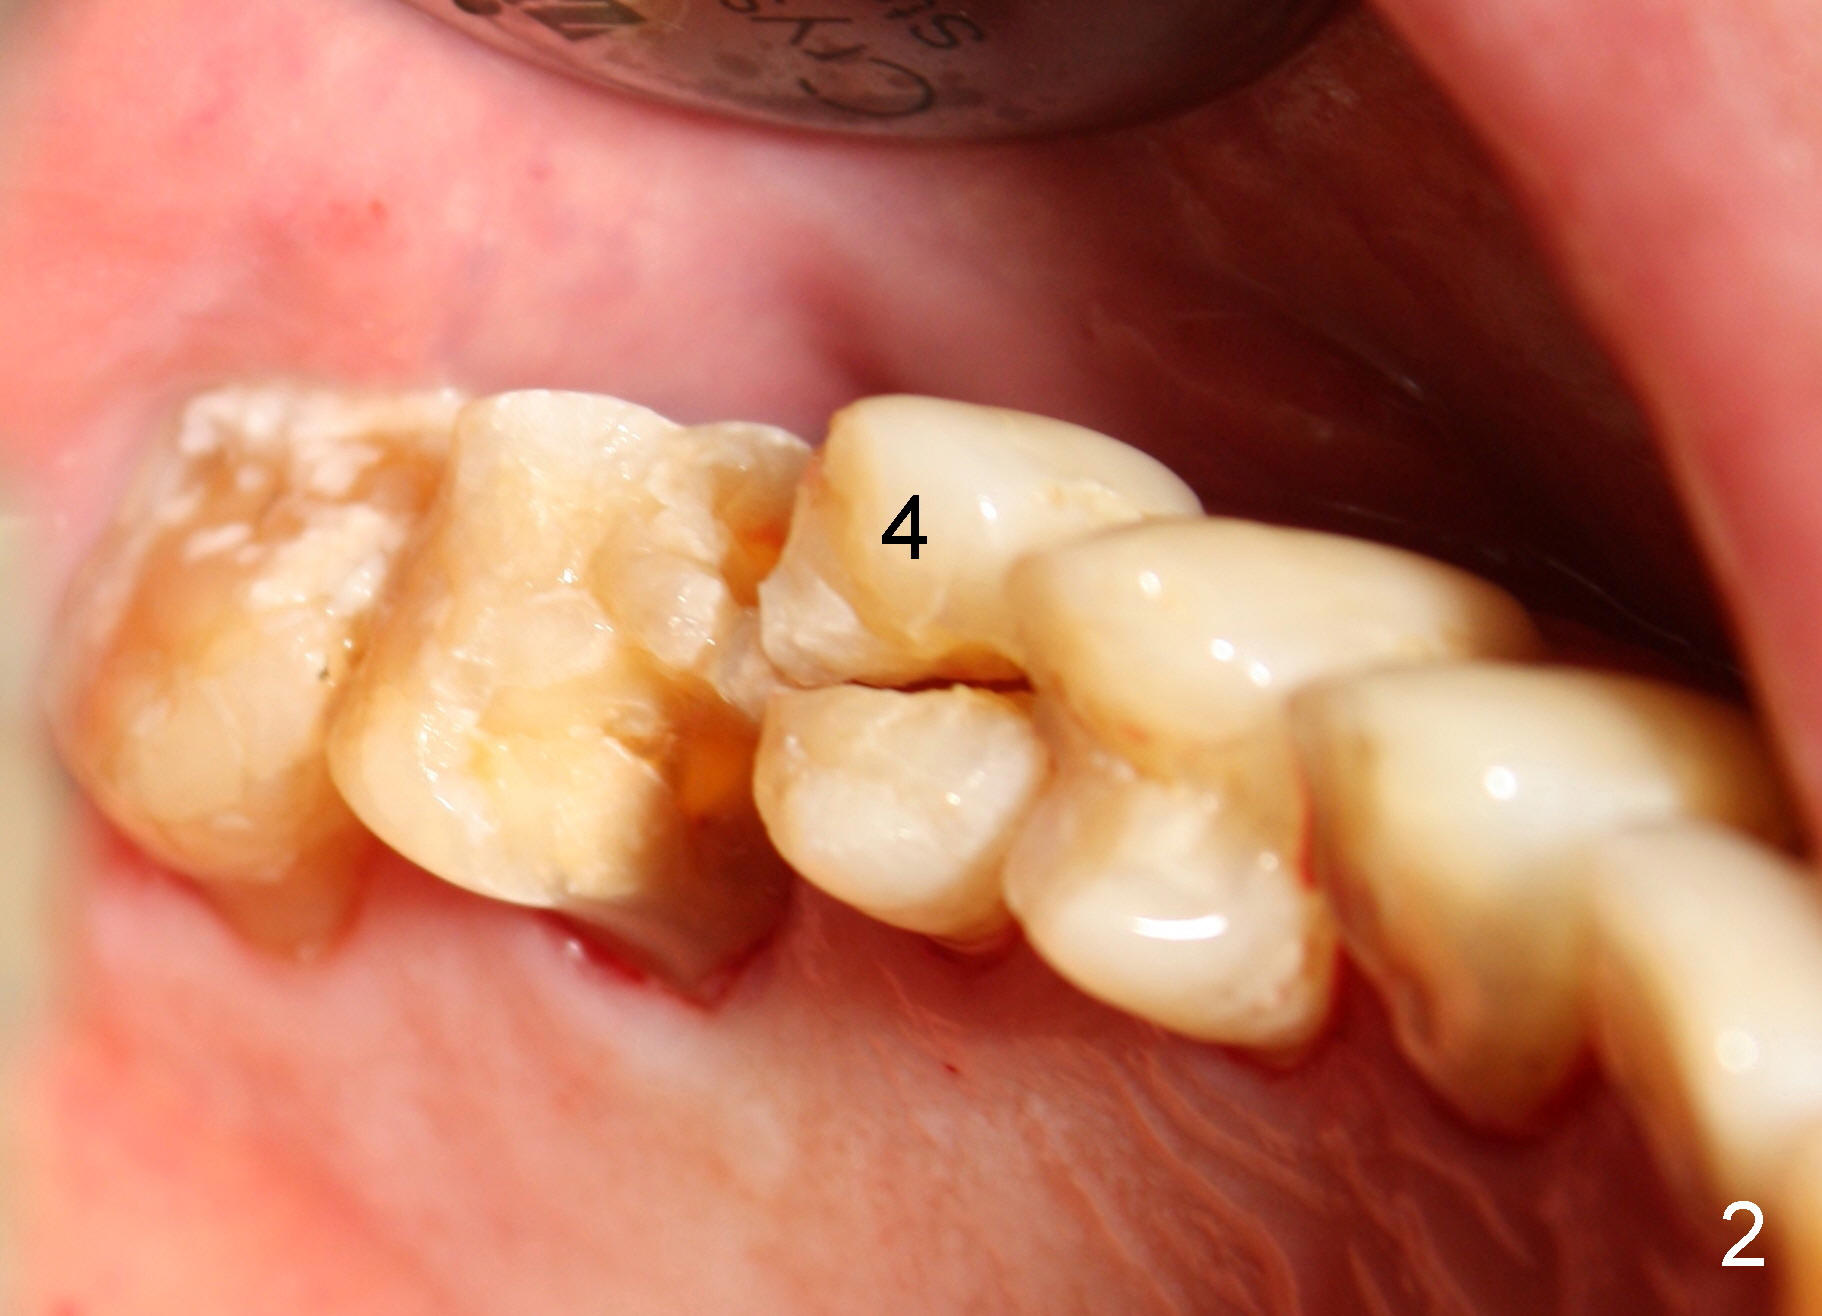

A 72-year-old man is a bruxer with #3 cusp fracture with chronic periapical radiolucency (Fig.1 *) and #4 acute crack. It appears reasonable to take care of emergency (#4 extraction and immediate implant (Fig.3-7: 4.5x20 mm, 45 Ncm)) followed by root canal therapy or extraction for #3. Eight (Fig.8) and 14 (Fig.9-11) days postop, the patient is doing fine and the wound heals normally. But he does not agree any treatment for #3, since it is asymptomatic in spite of a fistula associated with the tooth (Fig.8,9 >). Three months postop, the patient is still asymptomatic and is ready for #4 restoration since the tooth #28 cracks. Follow-up PA shows the persistent distal gap (Fig.12 >, as compared to Fig.4), accompanied with crestal bone resorption (*). Clinically the implant has mild mobility and light tenderness. The patient still refuses #3 treatment. It appears that the implant has failed to osteointegrate. In brief, do not place an immediate implant next to active infection.